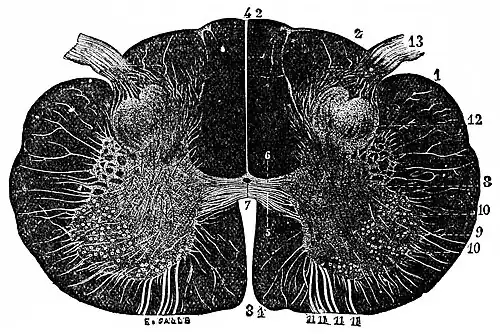

Fig. 5.—Transverse Section through Human Spinal Cord in Cervical Region, showing the organ to be composed of two symmetrical halves. (Sappey, after Stilling.) The black portions correspond to regions containing longitudinal fibers; the lighter portions represent the central gray matter and the horizontal roots of nerves; 5, 6, commissures connecting the symmetrical halves of the gray matter; 1, 11, 11, anterior or motor roots of spinal nerves coming from anterior horns or cornua of gray matter, in which are numerous groups of large ganglion cells; 13, posterior or sensory roots of spinal nerves, entering the posterior horns of gray matter. Magnified about eight diameters.